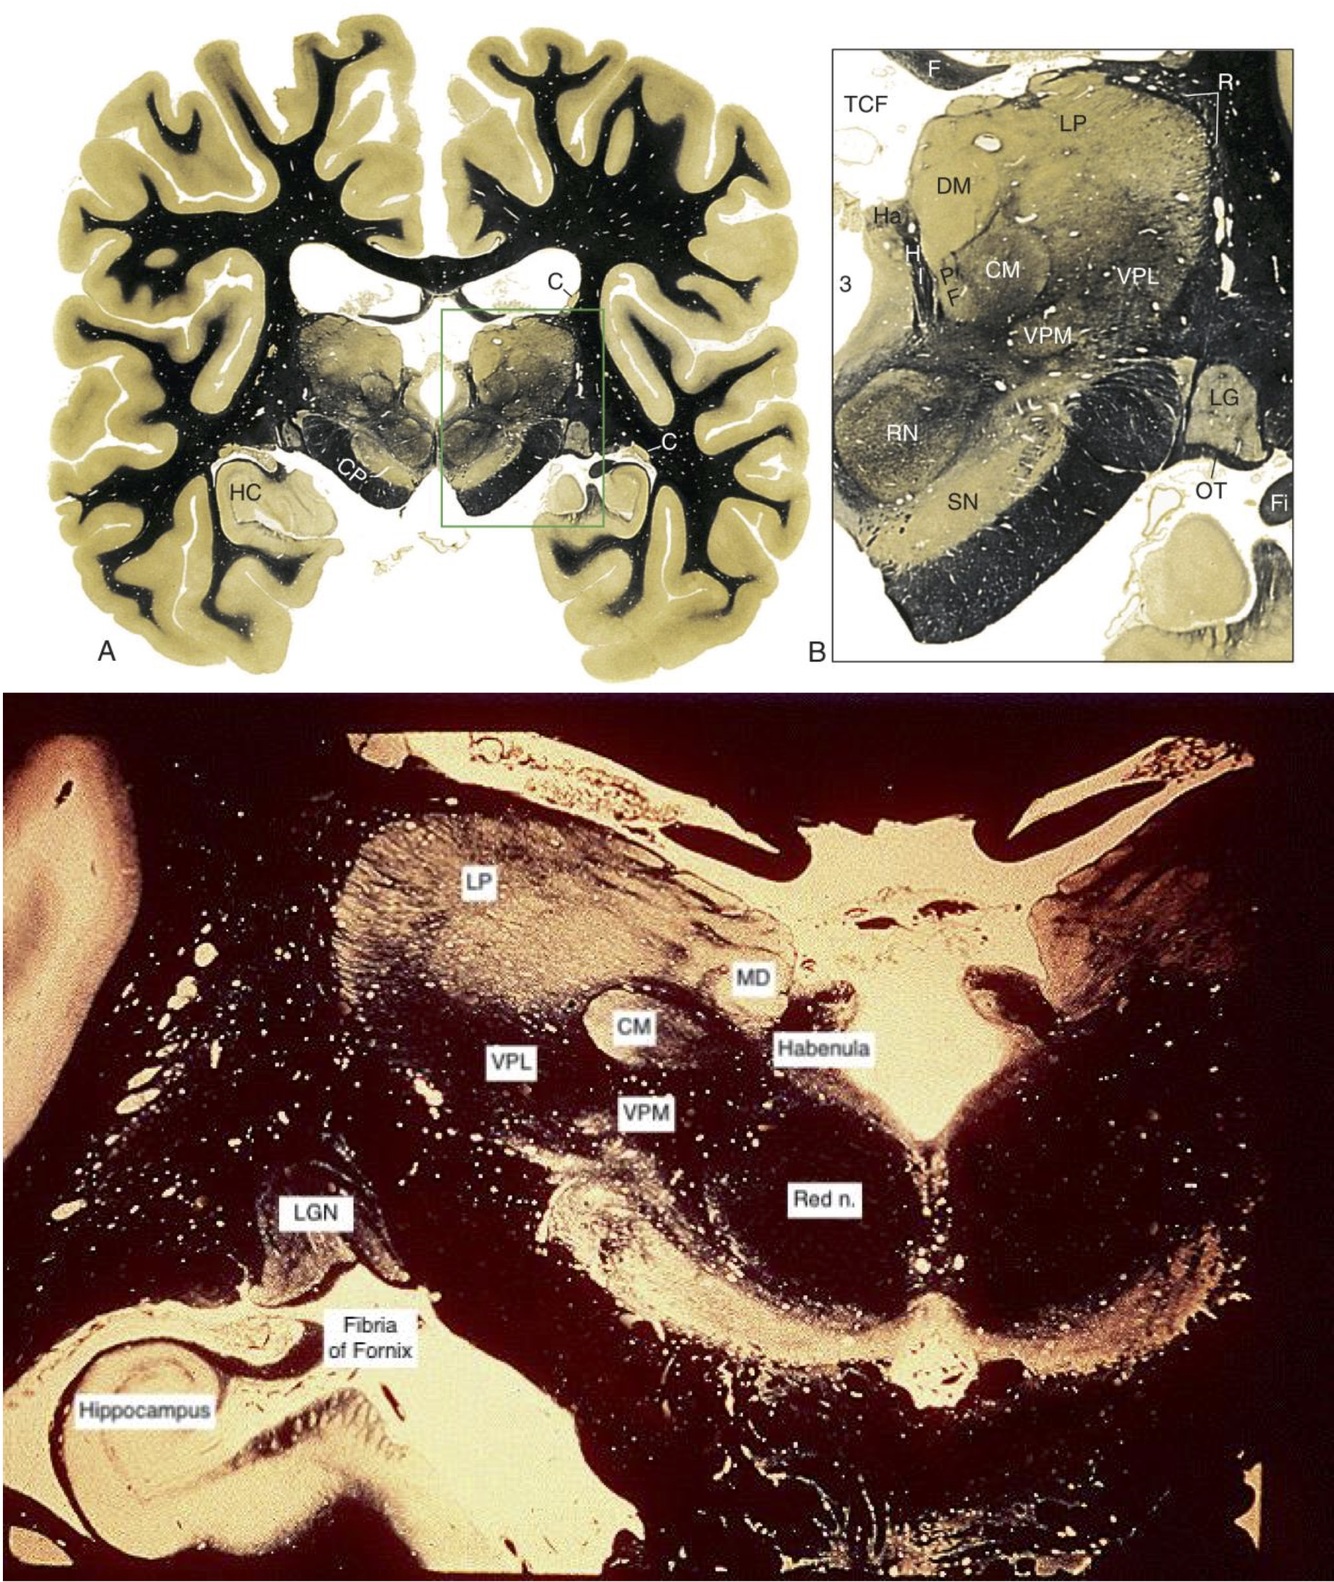

Thalamus

Mid-Caudal